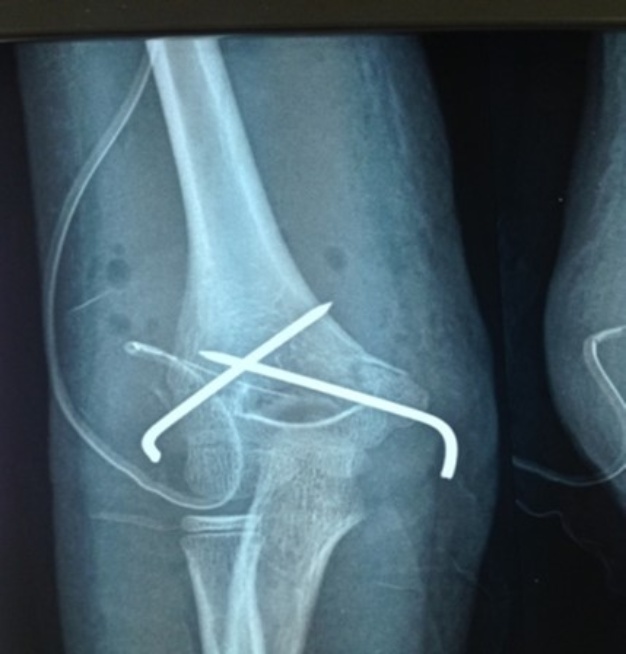

Orthopedic treatment, involving reduction under general anesthesia and immobilization following the Blount method (as seen in Figure 1), was administered to 19 patients. This method, while beneficial in our context, demands skilled operators due to the absence of fluoroscopic control during the reduction of type III and IV fractures.

Figure 1. Radiological images depicting a type IV FSCH as classified by Gartland, observed in a 7-year-old patient treated using the Blount method (pediatric surgery department, CHU ME).